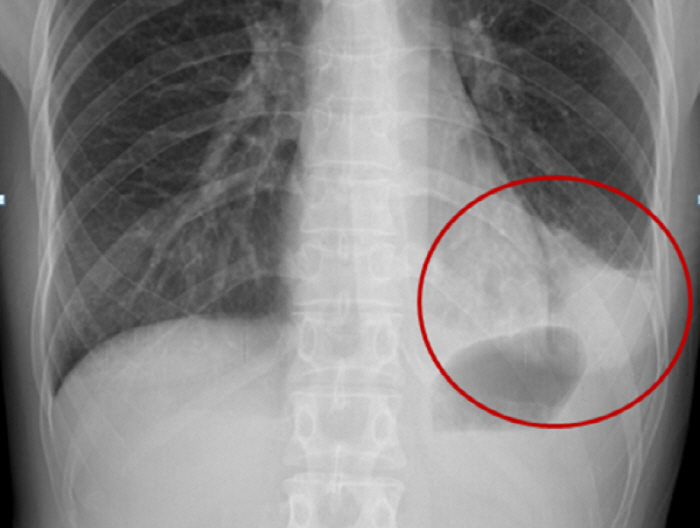

Pneumonia is diagnosed through clinical symptoms and X-rays. One of the most important decisions in treatment after being diagnosed with pneumonia is the decision of hospitalization. Outpatient or inpatient treatment should be determined appropriately according to the severity of the patient or the risk of death, but older people often have multiple comorbidities, so it takes longer to reach clinical stability, so a longer recovery period is needed than younger people. Therefore, when determining the timing of discharge after inpatient treatment in older adults with multiple comorbidities, it is necessary to assess whether additional measures, including early rehabilitation, are necessary.